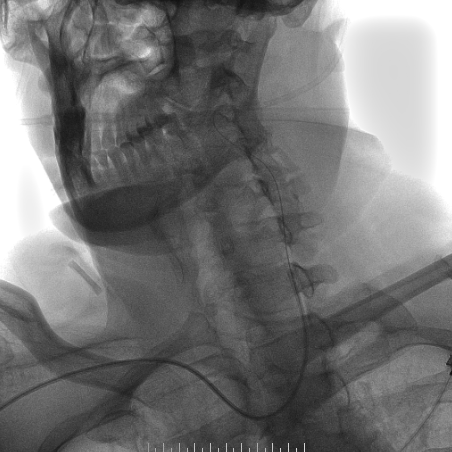

心脑联合造影

-- 右侧颈内起始部中度狭窄,经前交通向左侧代偿

-- 左侧颈内起始部重度狭窄